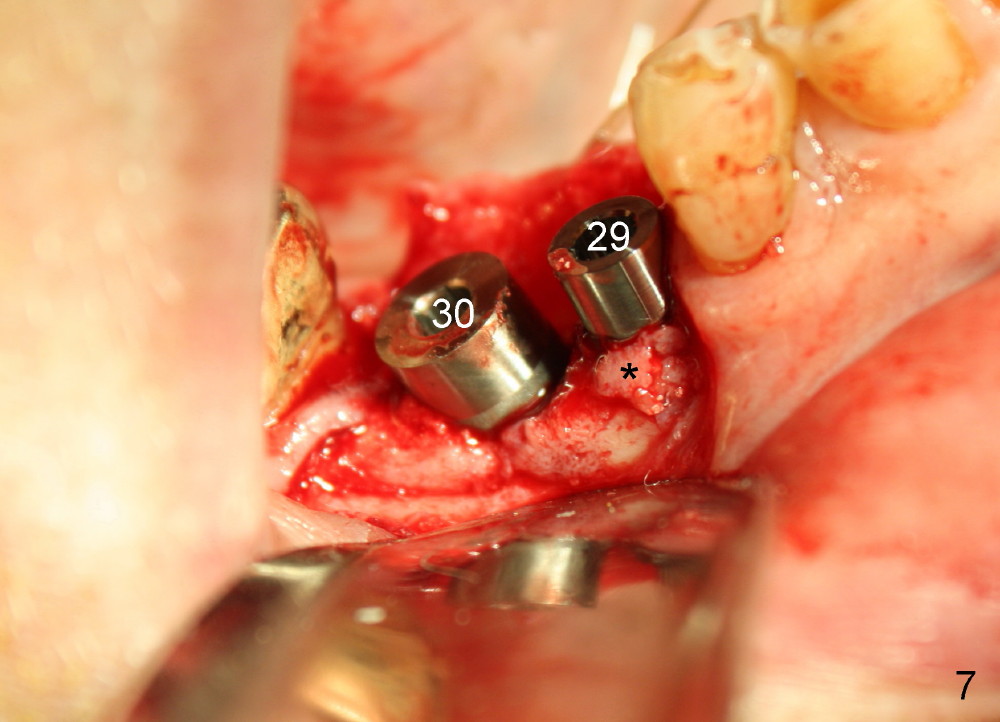

Three months later, the B-L width at the site of #29 is significantly reduced (Fig.4). Upon X-ray exam, there is decreased bone density between these two sockets (Fig.5 *). Socket preservation seems not to live its expectation. The obvious advantage is formation of callus-like bone in the molar socket (Fig.6 *, between the buccal (B) and lingual (L) plates). The significant decrease in the buccolingual width at the site of #29 is associated with buccal plate crack during implantation (Fig.7 *). At the site of #30, the lingual plate is so low that there is implant thread exposure (Fig.8 <). Mixture of autogenous bone (harvested from drilling with Bicon reamers) and synthetic bone (Osteogen) is placed mainly buccal to the implant #29 and lingual to #30 (Fig.9), followed by collagen membrane. Bone density between these two implant increases due to the bone grafting (Fig.10 *, as compared to Fig.5). In fact, the implant at the site of #29 is found loose 1 month postop.